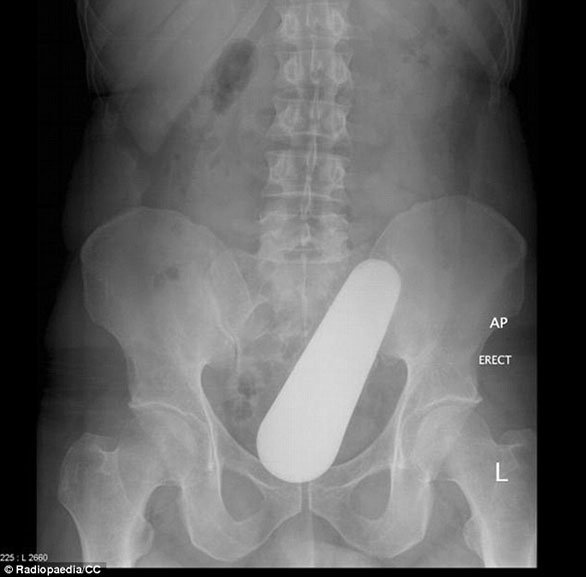

ضم الموقع مجموعة من الصور للأشعة السينية توضح أجساماً غريبة رُصدت داخل أجساد المرضى، ما أثارت دهشة الأطباء الذين قرروا رفعها على موقع طبي متخصص كمادة تعليمية ومرجعية بحثية واستشارية للدارسين في كليات الطب، والذي أنشئ من قبل طبيب أشعة أسترالي عام 2005، بحسب صحيفة دايلي ميل البريطانية.

صورة لأشعة "إكس راي" لأربعيني توضح وجود ما يُشبه "مدقة" طعام بينما يعد وجبة ماليزية.